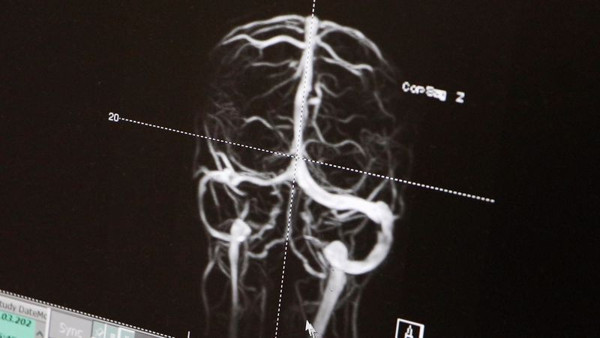

Hastalığın erken tanı konulmayıp uygun tedavisinin yapılmadığında geri dönüşümsüz körlüğe yol açtığını belirten Dr. Öğr. Üyesi Hülya İnce, "Psödotümor serebri; kafa içerisinde herhangi bir yer kaplayan lezyon olmadığı halde, sanki bir kitle varmış gibi, beynin basıncının artışı olarak tanımlanır. Nasıl ki göz tansiyonu, dolaşım sisteminin tansiyonu varsa, kafa içindeki yapıların anormalliğine bağlı beynimizin de tansiyonu yükselebiliyor. Biz de çocuk nöroloji uzmanı olarak, öncelikle kafa içerisinde vasküler, tümoral ya da herhangi yapısal bir lezyon var mı diye beyin MR ile değerlendiriyoruz. MR venografi dediğimiz bir yöntemle, beynin toplar damarlarında kan akımında bir anormallik olup olmadığını araştırıyoruz. Uygun hastalarda, beyin omurilik sıvısının (BOS) basıncını ölçerek, yüksek olup olmadığını değerlendiriyoruz. Özellikle doğurganlık çağındaki obez kadınlarda sık görülen bu hastalığın çocuklarda da çok sık olduğu bilinmektedir." diye konuştu.

Sözlerinin devamında İnce "Maalesef ki, görme sinirindeki kalıcı hasara bağlı olarak gelişen görme kaybı yeniden elde edilemez. Bu nedenle uygun tedavi edilmeyen çoğu hasta cerrahiye sevk edilebiliyor. Buradaki en büyük avantajımız, geniş etiyolojik testleri tüm hastalarımıza uygulayarak altta yatan nedeni ortaya koymamız oldu. Hastamız Elisa özelinde düşünürsek, bu etiyolojik testler sonucunda hastamızın beyin toplar damalarında bir pıhtı olduğunu gördük. Genetik olarak da pıhtı oluşumuna yol açan bir faktörün hem anneden hem babadan Elisa’ya aktarıldığını saptadık. Çocuk Hematoloji departmanımızla birlikte önce trombolitik, sonra da antitrombotik koruyucu tedavi ile hem kafa içinde artmış basıncı düzelttik, hem de pıhtıyı erittik" diye konuştu.